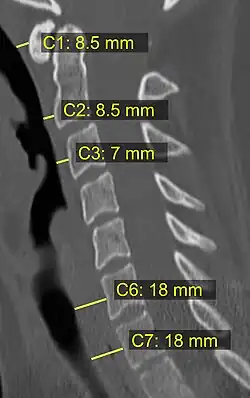

Na tomografia computadorizada ou radiografia, uma fratura cervical pode ser visualizada diretamente. Além disso, sinais indiretos de lesão pela coluna vertebral são incongruências das linhas vertebrais,[6] e/ou aumento da espessura do espaço pré-vertebral:[7]

- Tomografia computadorizada com limites superiores da espessura do espaço pré-vertebral em diferentes níveis.[9]